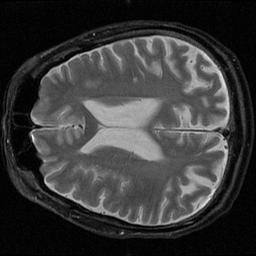

All algorithms were coded using MATLAB 6.0 and the source code is linked in the Appendix section. First, sample MR images of the brain were obtained (these were provided by Prof. Dwight Nishimura). Random noise was then created using MATLAB and added to the original image to create the noisy image to be filtered.

Original Image Noise Noisy Image

Two such images were created (with different noise components for each) to represent the consecutive image acquisitions required for the SNR estimation method. These images were then manipulated using the steps outlined in the introduction above (see Appendix for source code). The images were filtered using the correlation filter and Wiener filter already described. Additionally, several other spatial filters were implemented to determine their effectiveness in comparison to those already discussed. A median filter that used a 2x2 neighborhood of pixels was used. An average filter over a 3x3 neighborhood was also used. Additionally, a gaussian filter covering a 5x5 neighborhood was tested. Finally, a contrast, or ‘unsharp’, filter was also used. These filters are implemented in the source file ‘ExtraImageFilters.m’ in the Appendix. The results were then tabulated and compared for changes in SNR, CNR, and resolution loss compared to the noisy image.